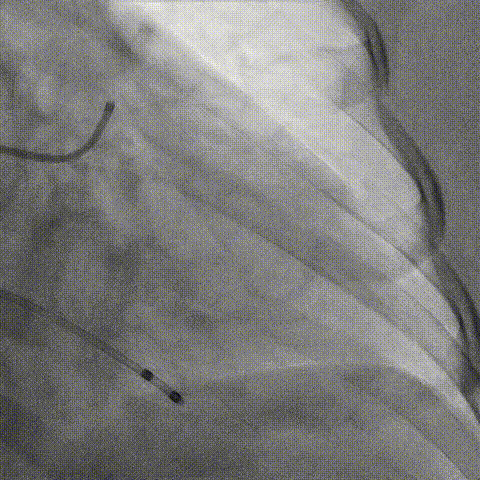

预置Telescope™导引延长导管及导丝保护左冠,

18mm球囊预扩张再次评估冠脉闭塞风险。

Telescope™+Runthrough

18mm*40mm 预扩张

预埋 Resolute Integrity 3.5*26mm

再次评估左冠开口